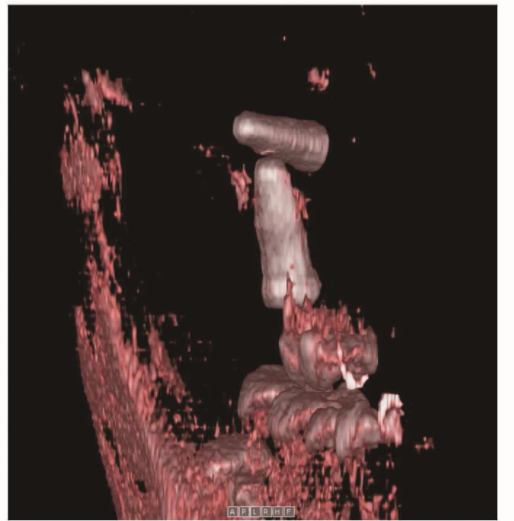

种植体进入上颌窦以后,其位置和方向可以完全不一样,三维重建图像可清楚显示种植体的形状与邻近结构的相关关系(图2、图3)。

图2 CBCT三维重建图显示种植体位于上颌窦内,移位的种植体呈内外向位于另外一个种植体的上方